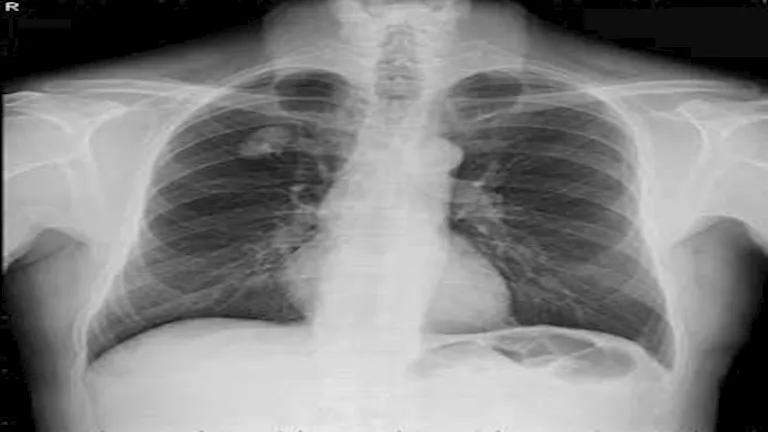

في أروقة مختبرات المستشفيات وعدسات الأطباء داخل أقسام الطوارئ، ظهرت نتائج تحاليل طبية وصفت بـ”الخارجة عن المألوف”، بعضها وصل حد الصدمة لما يحمله من أرقام غير قابلة للتصديق، وهذه الحالات، رغم ندرتها، تبقى بمثابة لغز يستفز العقل ويزيد من شأن المتابعة الطبية الاحترافية.